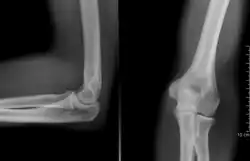

- Radiografia